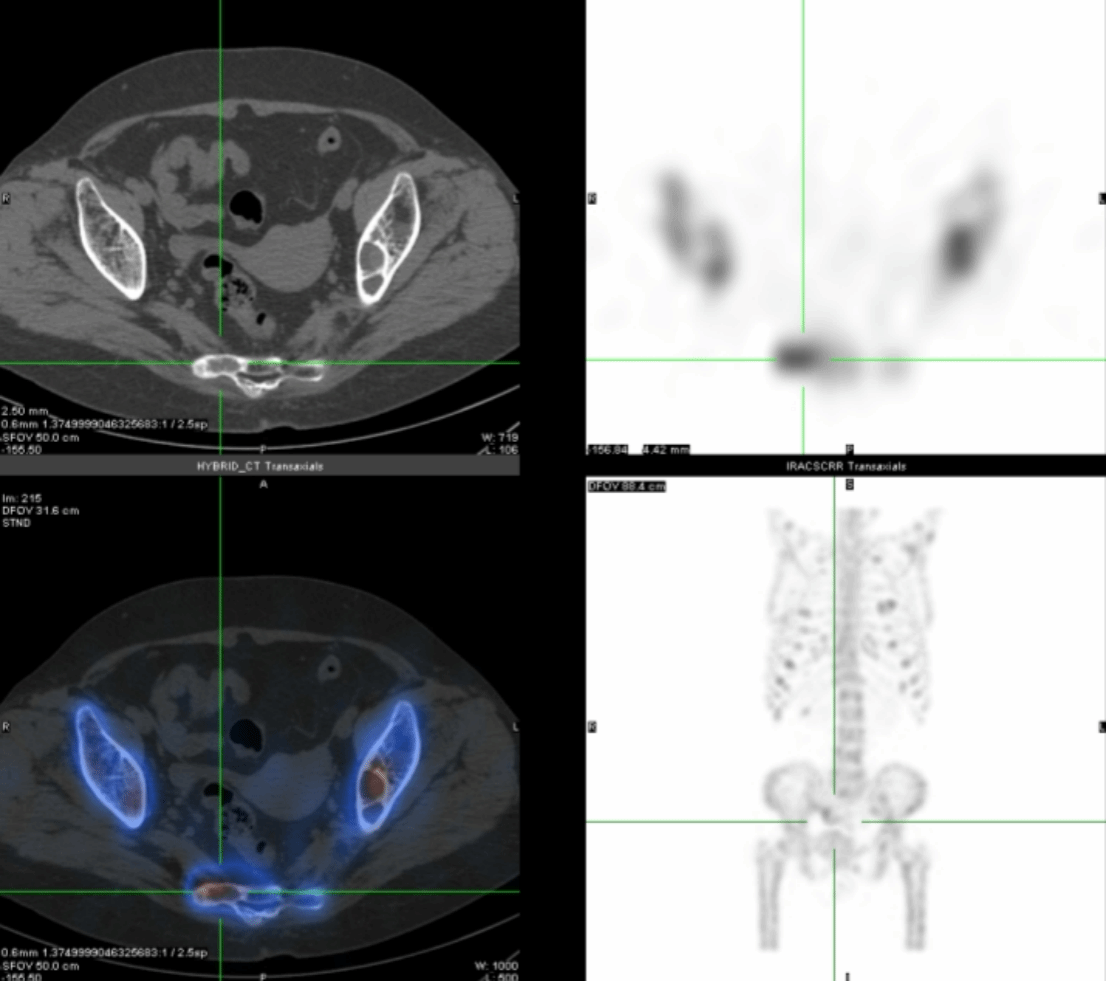

段阿姨,59岁,因腰背部疼痛1月,外院查CT示肋骨、骶骨骨质异常,骨转移?遂来核医学科行全身骨显像,判断是否是骨转移,图像(图1)如下:

全身骨骼显像剂分布弥漫性增强,肩胛骨、双侧部分肋骨、骶骨、右胫骨存在灶性显像剂异常浓聚,双肾及软组织本底显示不清,呈“超级骨显像”。

进一步的SPECT/CT断层融合显像(图2-4)显示:肋骨、肩胛骨、骶骨等灶性异常显像剂浓聚处伴骨质膨胀性骨质破坏。